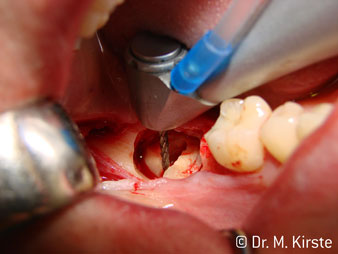

Die Winkelwahl des 45° Handstücks bringt viele Vorteile in der Anwendung. Chirurgisch tätige Kollegen, und für diese ist das Handstück in erster Linie entwickelt worden, werden schnell bemerken, dass man sehr gezielt arbeiten kann. Insbesondere bei der Weisheitszahnentfernung (Abb. 2) bedarf es keiner großen Weichteilabspreizungen im Wangenbereich (Abb. 3). Die Handstückkopfgestaltung kombiniert mit leichten Kopfdrehungen bei der Präparation lassen ein sicheres und schnelles Arbeiten im retromolaren Bereich zu.

Apropos schnelles Arbeiten: Es können über 100.000 U/min erreicht werden. Eine absolut professionelle Kühlung und ein kleiner Ansatzkopf lassen keine Fragen hinsichtlich thermischer Effekte oder übersichtlichem Arbeiten aufkommen.

Die professionelle Lagergestaltung im Innenleben des Handstückkopfes garantiert einen ruhigen Lauf der Bohrer, bei der Zahn- oder Wurzelseparation (Abb. 4 - 9) zeigt sich ein beeindruckendes Schnittbild ohne Schlageffekte.